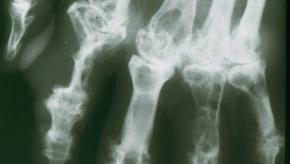

Osteoporosis is a disease characterized by increased bone loss that outpaces the grown of new bone. As a result bones become less dense and more fragile and brittle; porous bones are more prone to fracture.